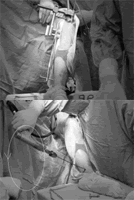

详细的操作过程是使用瞄准器(图1)正转钻过一端的皮质骨后改为反转,感觉骨髓内钉的位置,进而找到螺丝孔,再钻过洞把螺丝打进去(图2)。